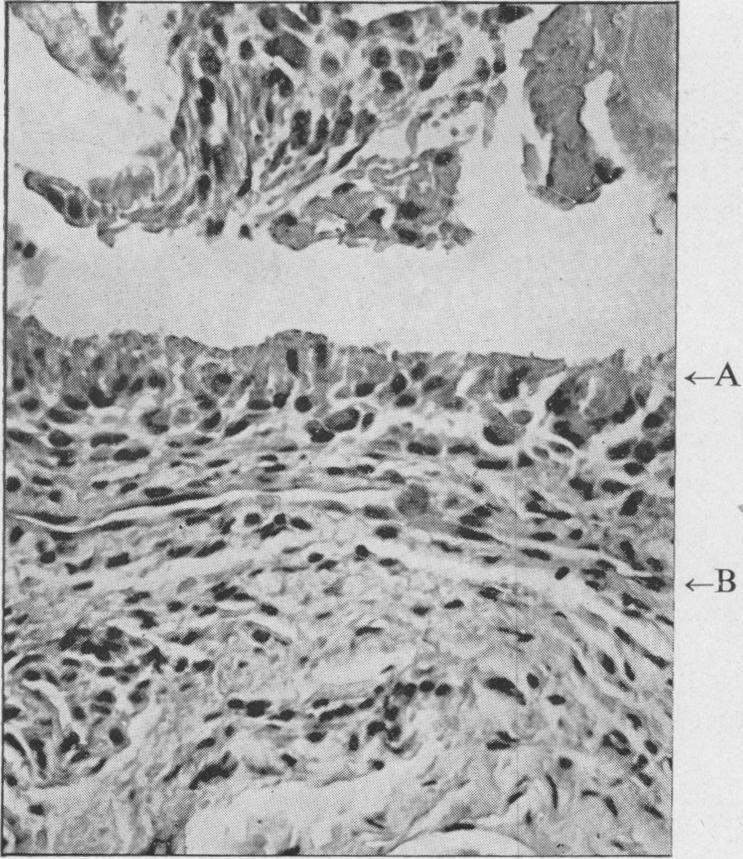

Multiple cysts of bones of extremities of unknown aetiology.